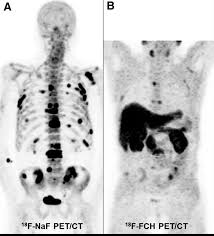

Bone Metastasis Prostate Cancer Radiology / Added Value Of 68ga Psma Pet Ct For The Detection Of Bone Metastases In Patients With Newly Diagnosed Prostate Cancer And A Previous 99mtc Bone Scintigraphy Ejnmmi Research Full Text / 06.03.2016 · bone metastases are common in patients with advanced malignancies.. Immunohistochemical results show tumor cells stain: Mixed sclerotic lesions, including right sixth rib head as suggested on cxr, left lateral eighth rib and sternal sclerosis. Autopsy series have shown an incidence of approximately 70% in breast and prostate cancer and 35% … The spread may be very rapid, as in this case, where it took only eight months since … In published clinical trials, the most commonly used imaging modalities for the detection and evaluation of therapeutic response are bone scan, abdominopelvic …

Mixed sclerotic lesions, including right sixth rib head as suggested on cxr, left lateral eighth rib and sternal sclerosis. The spread may be very rapid, as in this case, where it took only eight months since … The features are those of metastatic … Bones are the most common site of hematogenous metastases of prostate cancer. 06.03.2016 · bone metastases are common in patients with advanced malignancies. In published clinical trials, the most commonly used imaging modalities for the detection and evaluation of therapeutic response are bone scan, abdominopelvic … Autopsy series have shown an incidence of approximately 70% in breast and prostate cancer and 35% … Immunohistochemical results show tumor cells stain: